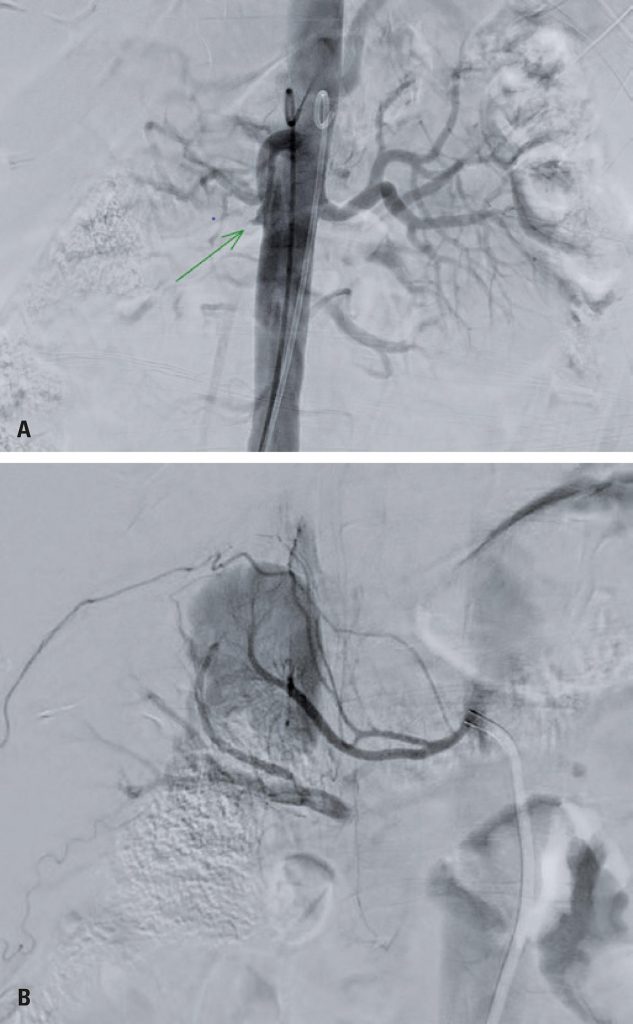

Spontaneous renal artery dissection is an unusual and idiopathic condition in most cases. In young, mildly symptomatic patients, diagnosis may be difficult, frequently culminating in delay in treatment. This report presents the case of a 40-year-old male patient, with severe hypertension of sudden onset, and difficult management of oral medication. In etiological investigation, Echo-Doppler of renal arteries showed signs of hemodynamically relevant right renal artery stenosis. Arteriography showed presence of double-lumen and thrombus in the vessel lumen, indicating dissection. The proposed treatment was endovascular approach after failure of isolated medical treatment, option which included the aspiration of the thrombus by Penumbra System® device and balloon angioplasty, followed by right renal artery stenting. Improvement of immediate sonographic control of peak systolic velocity and renal-aortic ratio was shown, with a consequent reduction of systemic arterial blood pressure and stabilization of renal function. Within the following year, the patient presented in-stent stenosis and was successfully treated with balloon angioplasty.